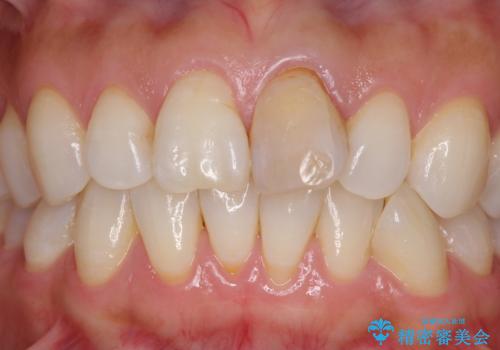

- 10年以上前に神経を取り除いた前歯の変色が気になるとのことで来院された患者様です。

レントゲン写真より、歯根の炎症が認められなかったため、ファイバーコアによる土台築製後、オールセラミッククラウンにて補綴することとしました。

変色とともに、捻れていたことも気になっていたので、その両方を解決させることとしました。

オーダーメイドタイプのクラウンを選択いただいたので、まるで天然の歯と見間違うほど自然に仕上がり、患者様には大変満足していただきました。